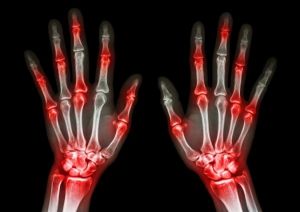

Un estudio publicado recientemente en The Lancet ahonda en la controversia, al concluir queparacetamol no alcanza la efectividad clínica mínima en la reducción del dolor y la mejora de la movilidad de pacientes con artrosis de rodilla o de cadera. De hecho, su efecto fue tan sólo ligeramente superior al de placebo, incluso en su dosis máxima diaria aceptada (4 gramos), por lo que los autores concluyen: «Con independencia de la dosis, no le vemos ningún papel en el tratamiento de estos pacientes».

En un metanálisis en red, incluso la dosis máxima diaria aceptada (4.000 mg) de paracetamol tuvo un efecto sólo ligeramente superior al de placebo